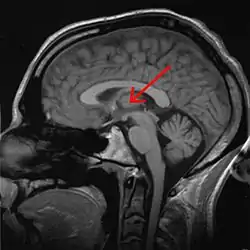

The thalamus (pl.: thalami; from Greek θάλαμος, "chamber")[1] is a large mass of gray matter on the lateral walls of the third ventricle forming the dorsal part of the diencephalon (a division of the forebrain). Nerve fibers project out of the thalamus to the cerebral cortex in all directions, known as the thalamocortical radiations, allowing hub-like exchanges of information. It has several functions, such as the relaying of sensory and motor signals to the cerebral cortex[2][3] and the regulation of consciousness, sleep, and alertness.[4]

The thalamus is a paired structure of gray matter about four centimetres long, located in the forebrain which is superior to the midbrain, near the center of the brain with nerve fibers projecting out to the cerebral cortex in all directions. The medial surface of the thalamus constitutes the upper part of the lateral wall of the third ventricle, and is connected to the corresponding surface of the opposite thalamus by a flattened gray band, the interthalamic adhesion. The lateral part of the thalamus is the phylogenetically newest part of the thalamus (neothalamus), and includes the lateral nuclei, the pulvinar and the medial and lateral geniculate nuclei.[6][7] There are areas of white matter in the thalamus including the stratum zonale that covers the dorsal surface and the external and internal medullary laminae. The external lamina covers the lateral surface and the internal lamina divides the nuclei into anterior, medial, and lateral groups.[8]